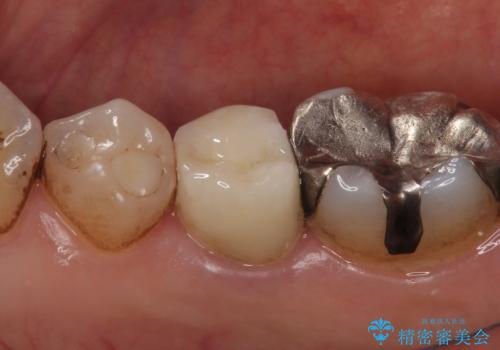

- 右下の歯でものを咬むと違和感があるので診て欲しいといらっしゃった方の症例です。

右下5番目の歯に根尖病変を認めたため、再根管治療を行い、オールセラミッククラウンによる補綴を行いました。